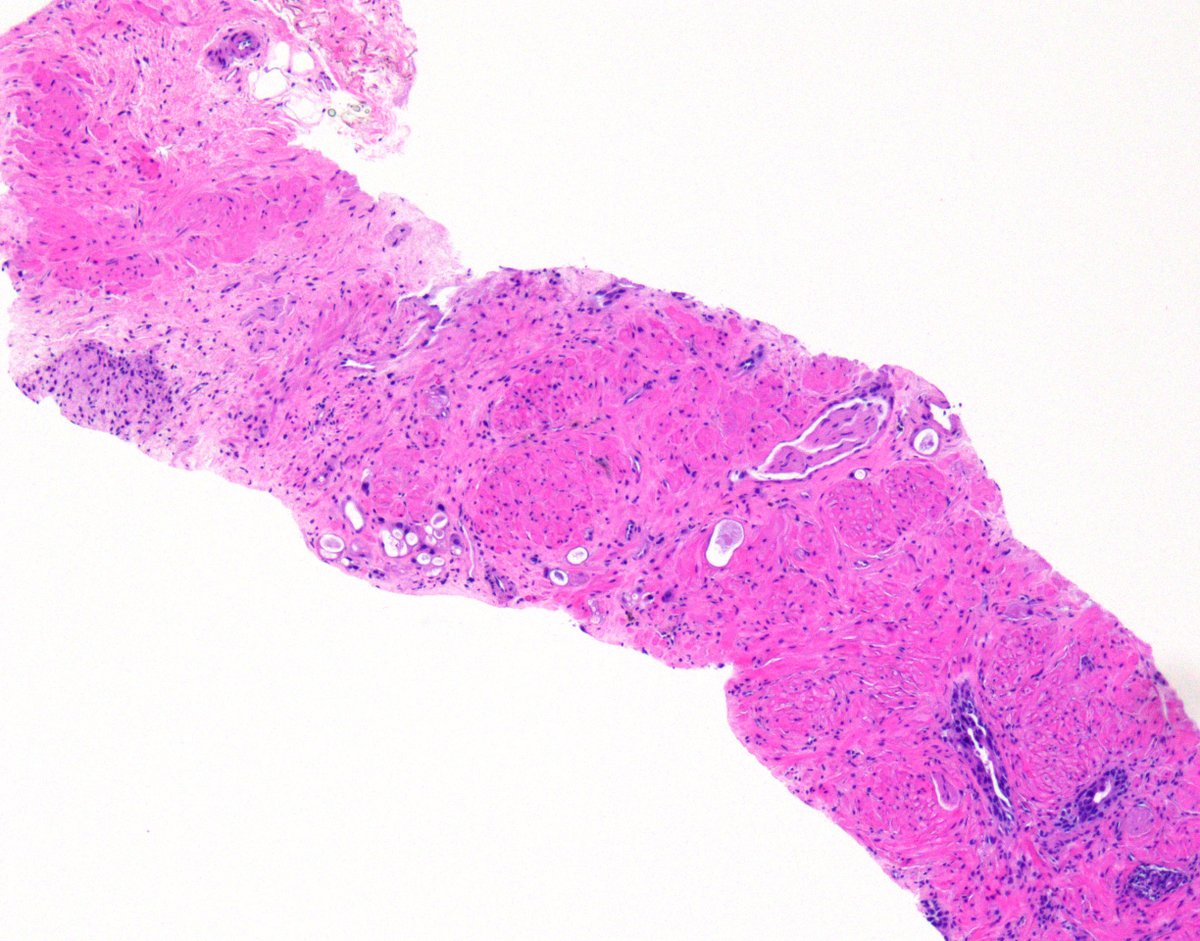

Textbook images of prostate NB with therapy-related changes #gupath ☢️ Poorly-formed glands/single cells w/vacuolization & prominent nucleoli = #ProstateCancer ☢️ Multi-layered glands w/eosinophilic cytoplasm, variable nuclear size & fine peri-glandular fibrosis = Benign